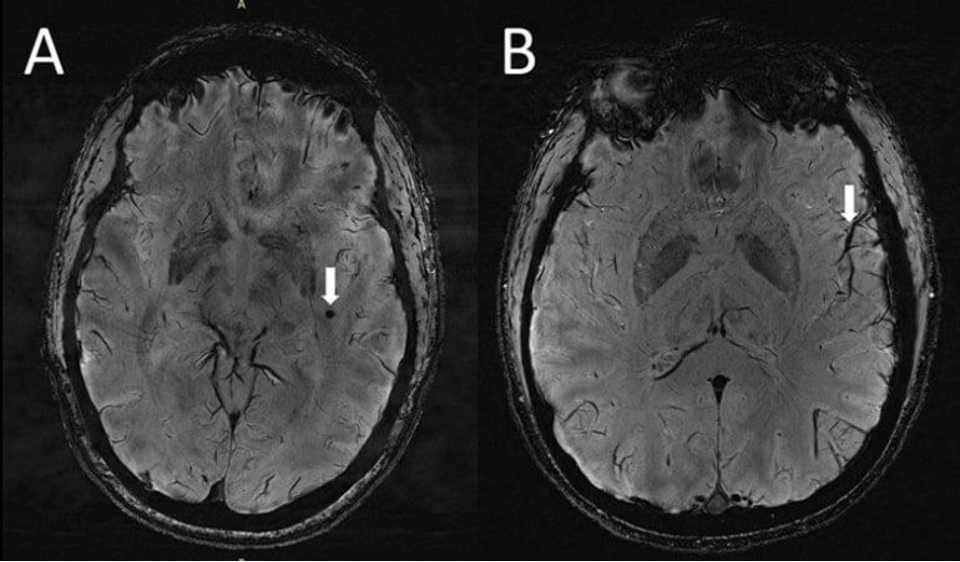

(A) Церебральные микрокровоизлияния, визуализируемые как круглые темные участки (стрелка) на SWI-последовательности в левой височной доле в случае мигрени с аурой. (B) Асимметрия внешнего вида корковых сосудов более заметна на левой стороне (стрелка) ипсилатеральнее микроизлияния. Credit: RSNA and Wilson Xu.

В исследовании приняли участие 10 добровольцев с хронической мигренью, 10 – с эпизодической без ауры и 5 здоровых людей. Исследователи обнаружили увеличение периваскулярных пространств в полуовальном центре и областях базальных ганглиев головного мозга. Гиперинтенсивность белого вещества — поражения, которые «загораются» на МРТ, — измеряли по шкале Фазекас. Церебральные микрокровоизлияния оценивали по анатомической шкале оценки микрокровоизлияний. Исследователи также собрали некоторые клинические данные: о продолжительности и тяжести заболевания, симптомах во время сканирования, наличия ауры и стороны головной боли.